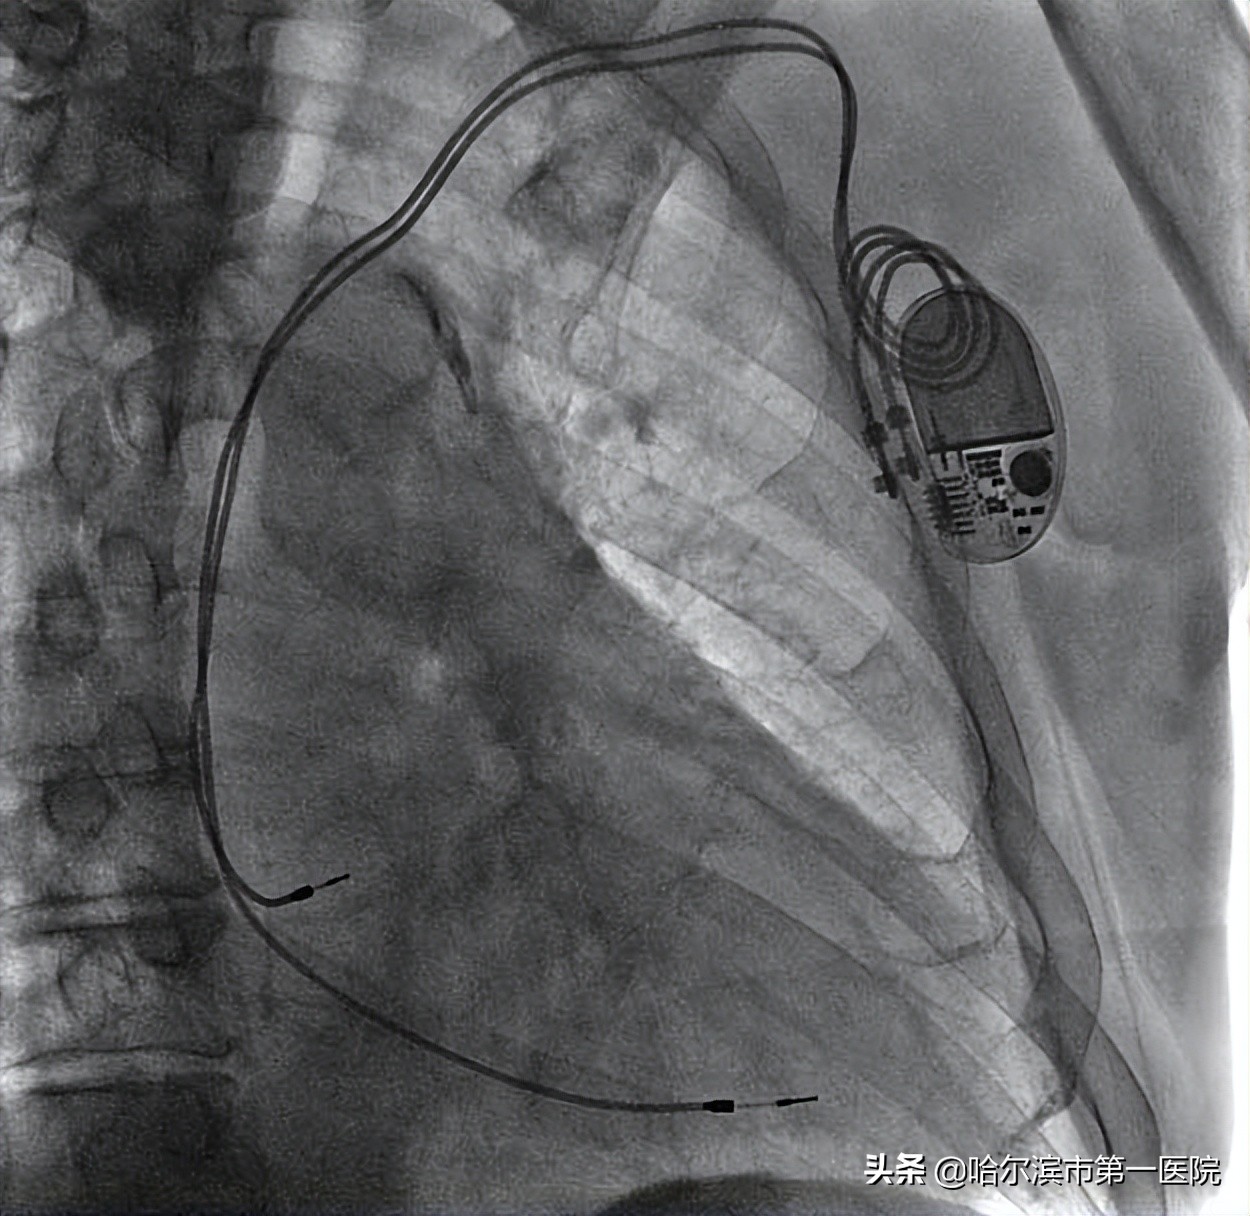

图3 赵侃团队ENDURITY MRI™ 双腔起搏器植入术中

图 4 ENDURITY MRI™ 双腔起搏器术后DSA影像